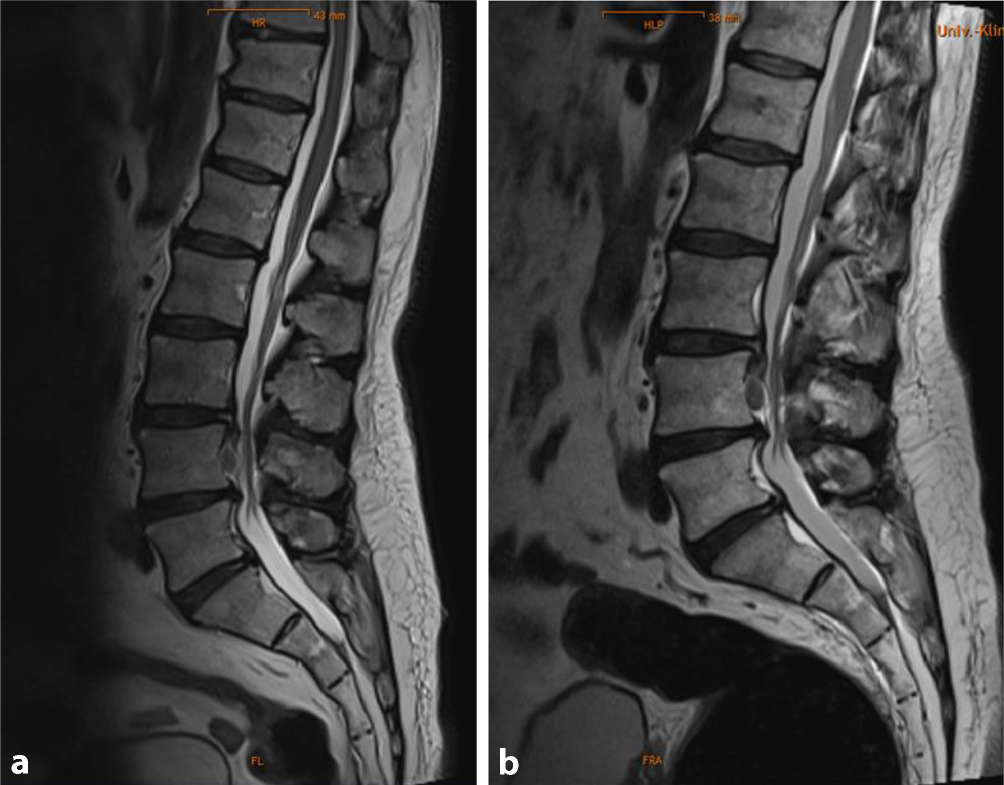

Patientenbeispiel mit wenig und mit massiv gefülltem Enddarm bei NSAR-Kolopathie: unterhalb des Kreuzbeines sieht man a den Enddarm normal gefüllt und b eine sogenannte Stuhlwalze. (Abbildung: Eisner/MUI)

Was ist bei so einer vermeintlichen Kaudasymptomatik passiert? Der Schlüssel dazu ist der klaffende Anus, der noch tonisieren kann und nicht schlaff offen ist. Durch die NSAR induzierte Darmträgheit, bedingt durch die Verdickung der Darmwand auf ca. 1 cm, kommt es zu einer reduzierten Bewegung des Darminhaltes, der sich zu einer Stuhlwalze großen Ausmaßes entwickelt und letztendlich am inneren (oberen) Bereich des Musculus sphincter ani internus anlangt und diesen aufdehnt (siehe Abb. 1). Durch seine Ausmaße wird auch der darum befindliche Musculus sphincter ani externus im oberen Bereich gedehnt, der sich kontrahiert. Diese Kontraktion erstreckt sich kettenartig bis zum Musculus sphincter urethrae externus, der dann mitverantwortlich ist, dass die Patient*innen nicht mehr Wasserlassen können. Durch das Setzen des Blasendauerkatheters kommt es zur Teilentspannung des Beckenbodens (Musculus bulbospongiosus, Musculus puborectalis) und es kommt zur Austreibung der angestauten Faeces. Anschließend ist die Pseudo-Kaudasymptomatik beseitigt. Wir Neurochirurg*innen schreiben diese Wirkung unserer hervorragenden Bandscheibenoperation zu. Alle Beteiligten sind zufrieden. Die Patient*innen sind extrem erleichtert und schmerzreduziert und die Chirurg*innen sind glücklich, wieder jemanden gerettet zu haben.